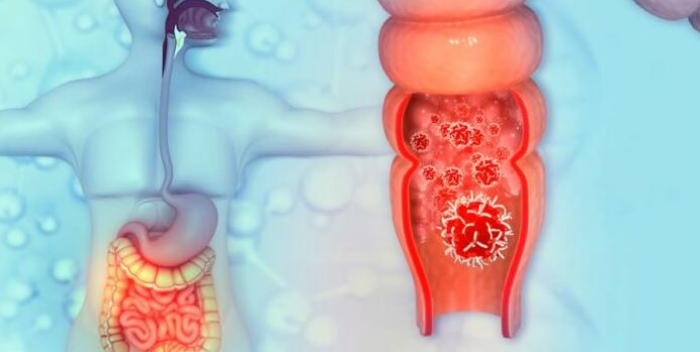

Terapia contra el cáncer de recto consigue dar la espalda a la radiación

El tratamiento contra el cáncer de recto, uno de los más comunes, ha alcanzado un punto de inflexión: en algunos pacientes es posible evitar la radioterapia, mejorando su calidad de vida sin ver comprometido el resultado.

Se calcula que en 2023, solo en Estados Unidos, 46.050 personas serán diagnosticadas con cáncer de recto. La detección temprana y los avances en la terapia han conseguido una disminución constante de las tasas de mortalidad y actualmente hay una tasa de supervivencia del 74 % al cabo de 5 años.